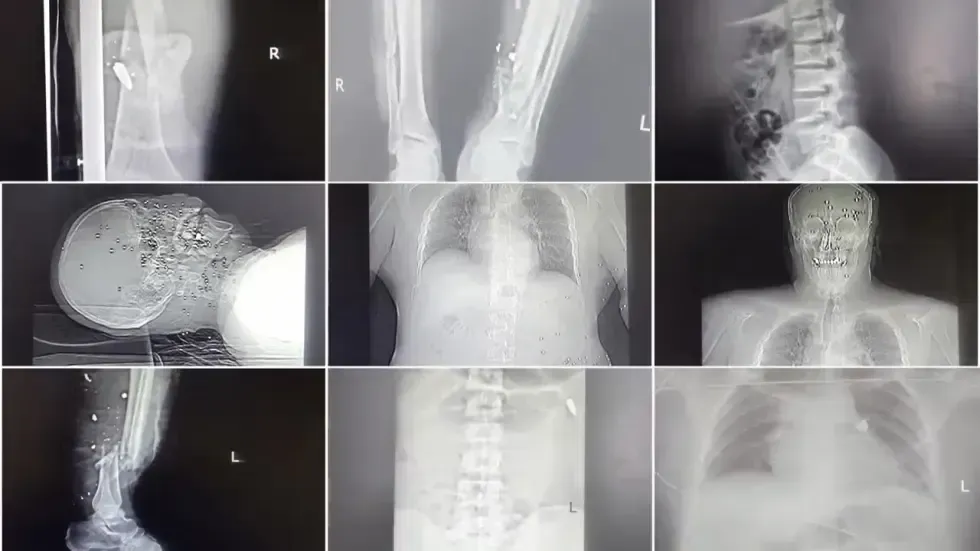

فعلى مدار بضعة أيام في أوائل شهر يناير/كانون الثاني، احتشد عملاء يرتدون ملابس مدنية في المستشفيات في عدة مدن لعلاج آلاف الجرحى الذين أصيبوا على أيدي قوات الأمن الإيرانية التي أطلقت النار على الحشود لقمع الاحتجاجات الضخمة ضد الجمهورية الإسلامية التي يبلغ عمرها 47 عاماً. وقام هؤلاء العملاء بمراقبة المحتجين وعرقلة تقديم الرعاية للمتظاهرين في بعض الأحيان، وقاموا بترهيب الموظفين واعتقال المتظاهرين وأخذ الموتى في أكياس الجثث. وتم اعتقال العشرات من الأطباء.

في إحدى المرات، أحضر رجال الأمن جثة رجل ميت ويداه مكبلتان بالأغلال أمام جسده. وقال إنه كان مصابًا بطلقات خرطوش في بطنه وصدره وجرح واضح في رأسه.

وقالت الباحثة في شؤون إيران في منظمة العفو الدولية، رها باهريني، إن منظمة العفو الدولية تلقت تقارير موثوقة تفيد بوقوع عمليات إطلاق نار مستهدفة، ومن مسافة قريبة، على المحتجين، و"على نطاق أوسع بكثير" مما كان يحدث في حملات القمع السابقة ضد الاحتجاجات. ويُظهر مقطعا فيديو جثث متظاهرين مصابين بطلقات نارية من مسافة قريبة ومعدات طبية متصلة بأجسادهم.

وقال الطبيب إنه وموظفين آخرين حاولوا إخفاء المحتجين المصابين من خلال تسجيل تشخيصات خاطئة في سجلات المستشفى. تم تحديد الطلقات النارية في البطن على أنها آلام في البطن؛ وتم تسجيل كسور في العظام على أنها حادث سقوط. وتم تعريف أحد المرضى الذين أصيبوا بطلقات نارية في الأعضاء التناسلية على أنه مريض مسالك بولية.

يتذكر الجراح أن امرأة في الثلاثينيات من عمرها أصيبت بطلقة من مسافة قريبة، مما أدى إلى تدمير سقف فمها والمنطقة المحيطة بأنفها وأسفل عينيها.

وأُصيب شاب في العشرينات من عمره بذخيرة حية في مرفقه، مما أدى إلى تهشيمه. قام الجراح بخياطة الجروح لكنه كان يعلم أنه يجب بتر الذراع.

قال الجراح إن عائلة مكونة من أربعة أفراد أم وأب وطفليهما البالغين من العمر 8 و 10 سنوات كانوا جميعاً مصابين بطلقات نارية. كان الصبي الأكبر مصابًا بعشرات الكريات في وجهه، لكن من المدهش أن أيًا منها لم تصب عينيه.